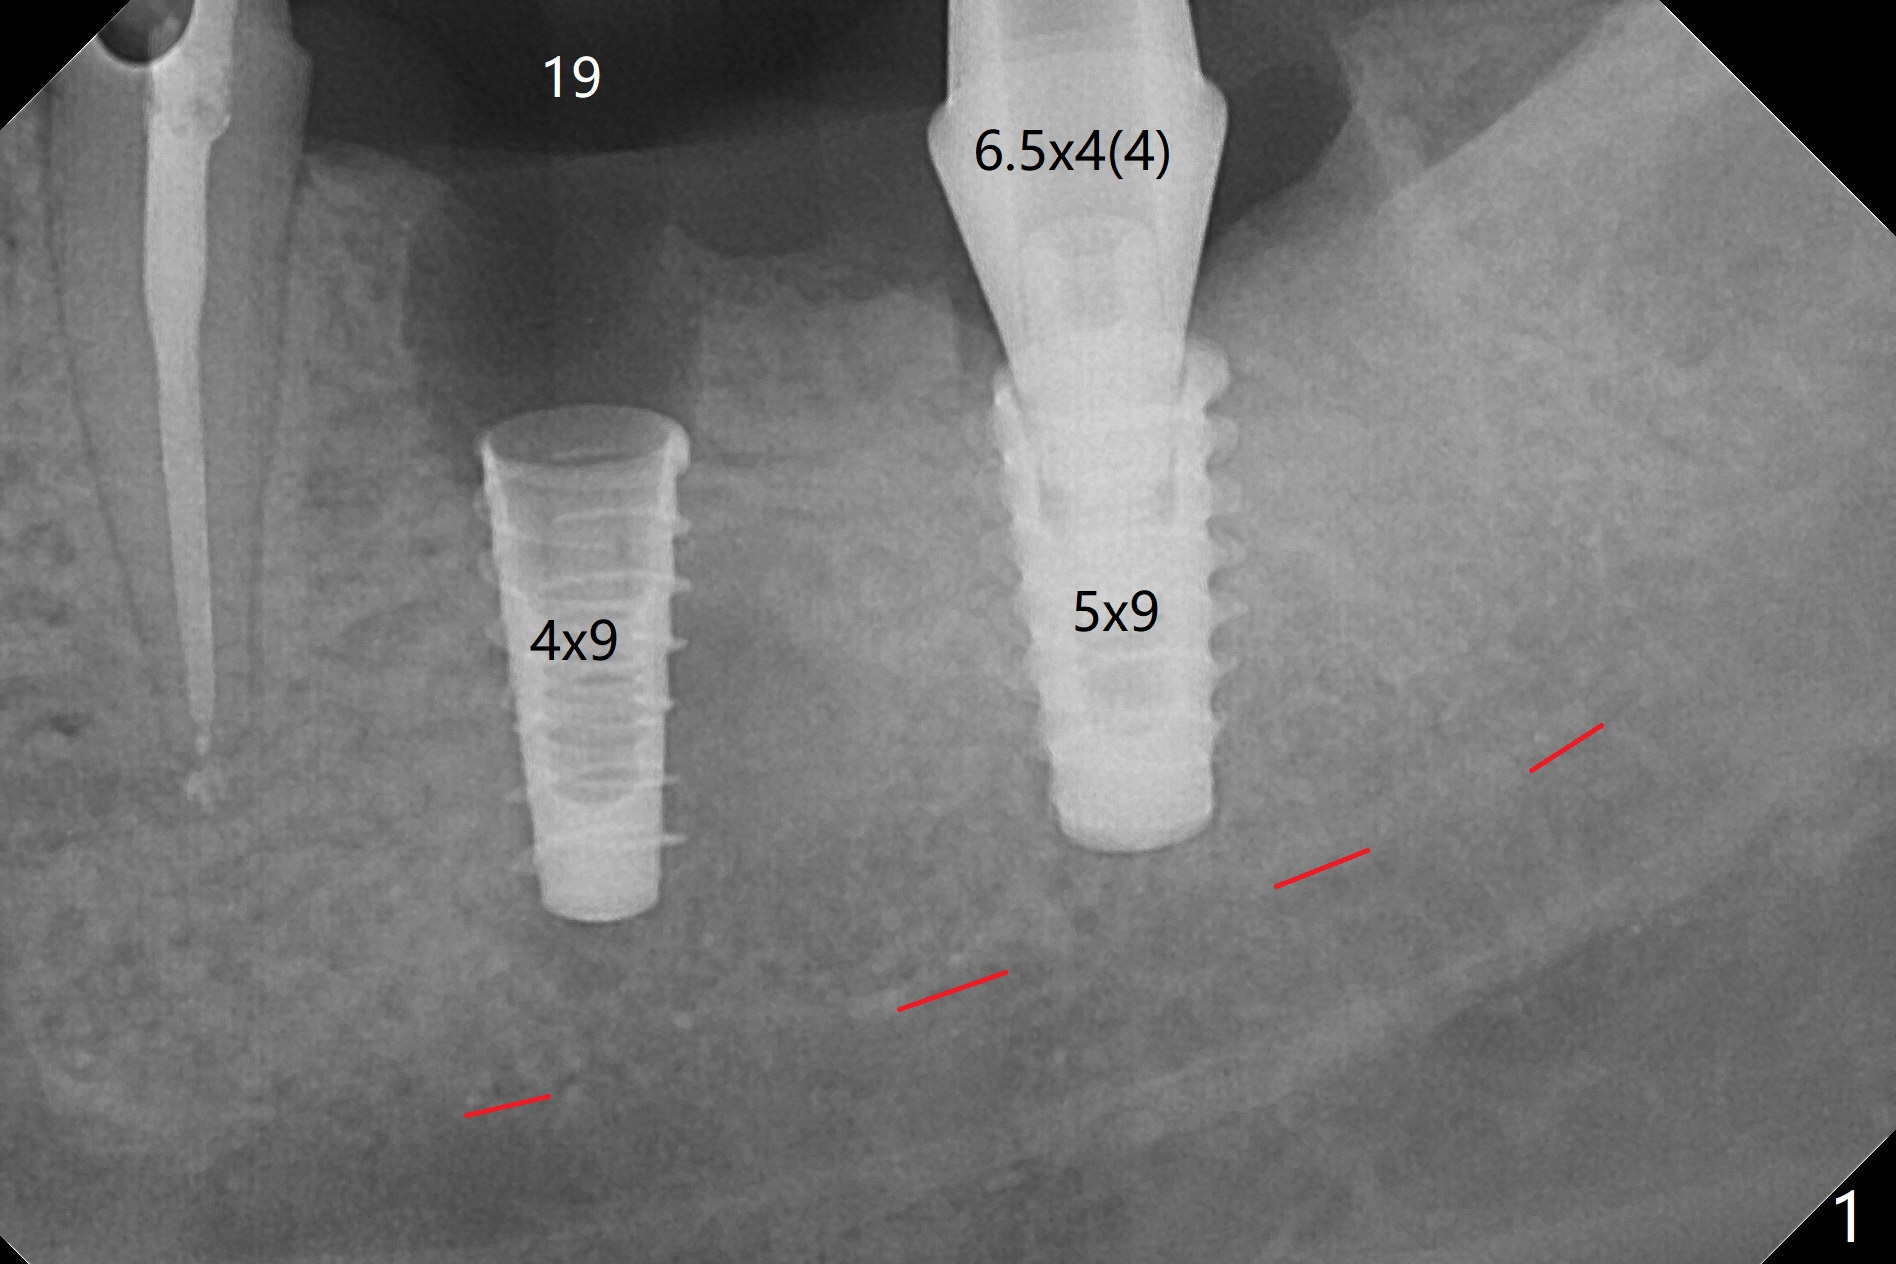

The female woman is afraid of pain. After placement of 4x9 mm FC implant at #19, infiltration anesthesia is not enough for osteotomy at #18. Block anesthesia is added. When a 5x9 mm FC implant is placed in the osteotomy (designed for 5x8.5 mm IS one), it is close to the Inferior Alveolar Canal (Fig.1 red dashed line; Fig.2 (*: bone graft with PRF)). The third contributing factor is the pressure upon the distal end of the distal end guide while osteotomy. A few hours later, the patient reports no paresthesia. The implant placement level and trajectory are normal at #18 and 19 (Fig.3-5). To check pair abutment seating with 30 Ncm torque, PA is taken after removal of healing abutments 4 months postop (Fig.6-8). First the cuff of the abutment is short, subgingival distal of #18 (Fig.6 * (gingiva)). When an abutment with longer cuff is placed, it appears to be close to the distal crestal bone (Fig.7 *). Finally a smaller abutment seams to be appropriate (Fig.8). Retrospectively the larger abutment (6.5x4(4) mm) is incompletely seated initially (Fig.1 with gap).